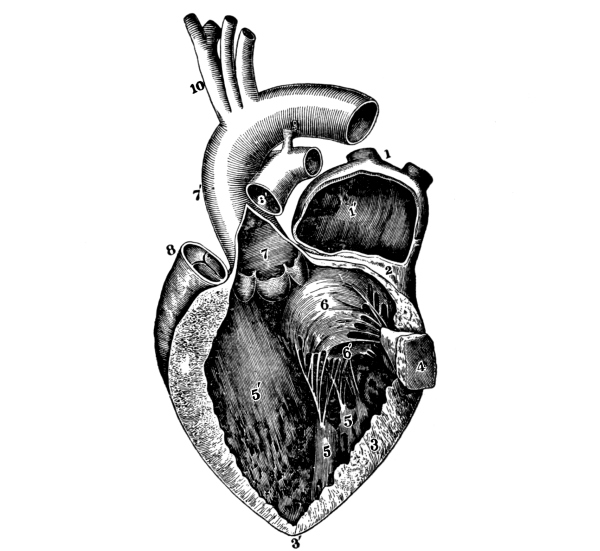

The Heart, 101—The Pericardium, 101—Cavities of the Heart, 103—The Endocardium, 103—The Valves of the Heart, 103—Circulation, 105—Circulation in the Fetus, 106—Arteries, 107—Veins, 109—Portal Circulation, 109—Pulmonary Circulation, 110—Nerves of the Heart, 110—Heart Sounds, 111—The Heart Beat, 111—Factors Affecting Circulation, 112—The Pulse, 113—Blood Pressure, 114—Nerve Supply of the Blood-vessels, 115—The Blood, 116—Composition of the Blood, 116—Coagulability of the Blood, 117—Blood-corpuscles, 118. |